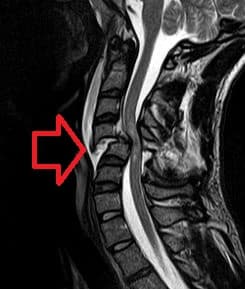

A spinal cord injury (SCI) is damage to the spinal cord that causes temporary or permanent changes in its function. Symptoms may include loss of muscle function, sensation, or autonomic function in the parts of the body served by the spinal cord below the level of the injury. Injury can occur at any level of the spinal cord and can be complete, with a total loss of sensation and muscle function at lower sacral segments, or incomplete, meaning some nervous signals are able to travel past the injured area of the cord up to the Sacral S4-5 spinal cord segments. Depending on the location and severity of damage, the symptoms vary, from numbness to paralysis, including bowel or bladder incontinence. Long term outcomes also range widely, from full recovery to permanent tetraplegia (also called quadriplegia) or paraplegia. Complications can include muscle atrophy, loss of voluntary motor control, spasticity, pressure sores, infections, and breathing problems. In the majority of cases the damage results from physical trauma such as car accidents, gunshot wounds, falls, or sports injuries, but it can also result from nontraumatic causes such as infection, insufficient blood flow, and tumors. Just over half of injuries affect the cervical spine, while 15% occur in each of the thoracic spine, border between the thoracic and lumbar spine, and lumbar spine alone. Diagnosis is typically based on symptoms and medical imaging. Efforts to prevent SCI include individual measures such as using safety equipment, societal measures such as safety regulations in sports and traffic, and improvements to equipment. Treatment starts with restricting further motion of the spine and maintaining adequate blood pressure. Corticosteroids have not been found to be useful. Other interventions vary depending on the location and extent of the injury, from bed rest to surgery. In many cases, spinal cord injuries require long-term physical and occupational therapy, especially if it interferes with activities of daily living.